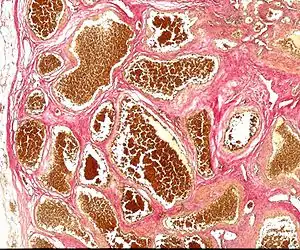

Cerebral Cavernous Malformation (CCM) is a cavernous hemangioma that arises in the central nervous system (CNS). It can be considered to be a variant of hemangioma, and is characterized by grossly large dilated blood vessels and large vascular channels, less well circumscribed, and more involved with deep structures, with a single layer of endothelium and an absence of neuronal tissue within the lesions. These thinly walled vessels resemble sinusoidal cavities filled with stagnant blood. Blood vessels in patients with cerebral cavernous malformations (CCM) can range from a few millimeters to several centimeters in diameter. Most lesions occur in the brain, but any organ may be involved.[1]

| Histology of a cavernous hemangioma | |